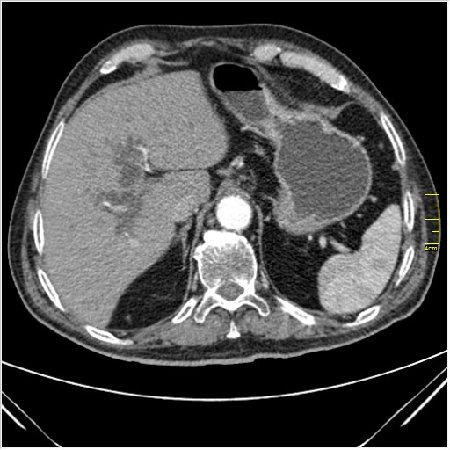

Мужчина 62 года с желтухой

Опухоль головки поджелудочной железы, расширение холедоха и панкреат. протока (Double Channel sign)

Карциномы панкреас гиподенсны на КТ с болюсом, т.к. содержать много соединительной и фиброзной ткани, в отличие от нормальной ткани железы, которая (как любая железа) хорошо васкуляризирована. Поэтому если видим в панкреас солидное гиподенсное образование - всегда настораживает на предмет рака. Второй момент: обязательная оценка взаимоотношения опухоли к ВБА и ВБВ, на предмет оценки операбельности.

pancr7.JPG

pancr7.JPG (62.38 КБ) 2898 просмотров